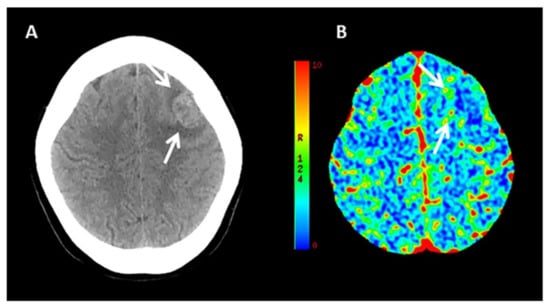

3.1. MRI and ICH Expansion

4.1. MRI